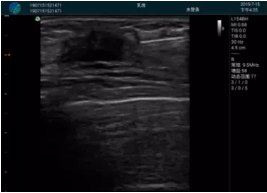

清晰顯示腺體內(nèi)低回聲快影,邊界清晰,包膜較光滑

確定進(jìn)針路徑并實(shí)時監(jiān)測抽吸針與腫塊位置關(guān)系

抽吸針進(jìn)入腫塊內(nèi)部進(jìn)行旋切

抽吸過程中可見腫塊明顯縮小,并根據(jù)腫塊位置改變針道位置

抽吸旋切后再進(jìn)行超聲復(fù)查,原腫塊區(qū)域未見殘留組織及出血